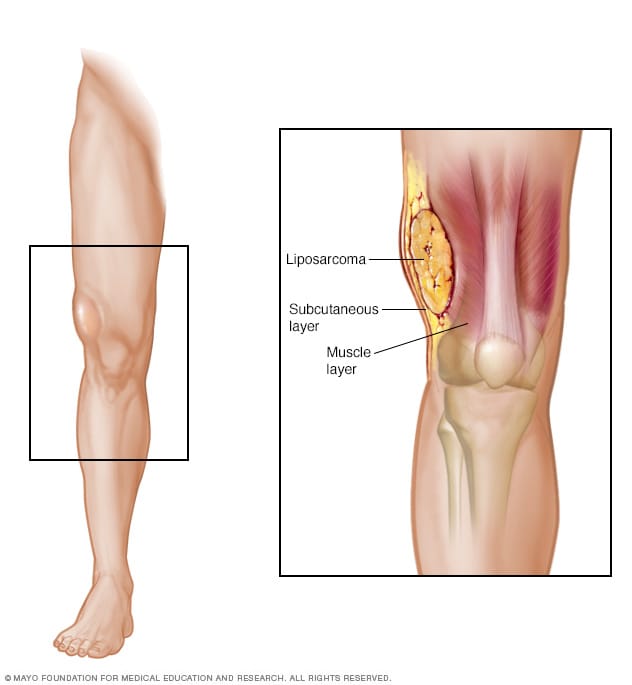

Liposarcoma – Symptoms and causes – Mayo Clinic

Liposarcoma:one the most common soft tissue sarcoma w peak incidence in …